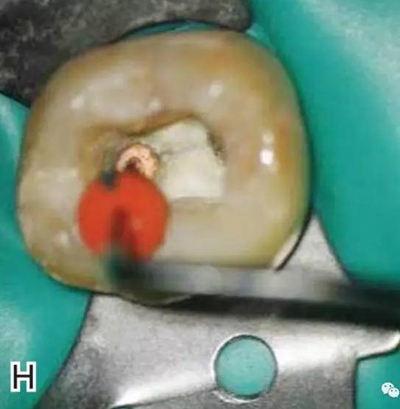

在完成根尖段的充填后,使用熱塑牙膠注射儀對根管中上段進(jìn)行分層充填,一般分2~3次完成充填,每次充填均使用相應(yīng)直徑大小的垂直加壓器進(jìn)行加壓。拍片確認(rèn)充填效果(圖8)。

圖8 熱牙膠根中上段的充填,A、B.注射儀注射中段熱牙膠

C、D.垂直加壓器加壓 E、F.注射儀繼續(xù)注射上段熱牙膠

G、H.垂直加壓器加壓 I、J.完成根中上段的充填